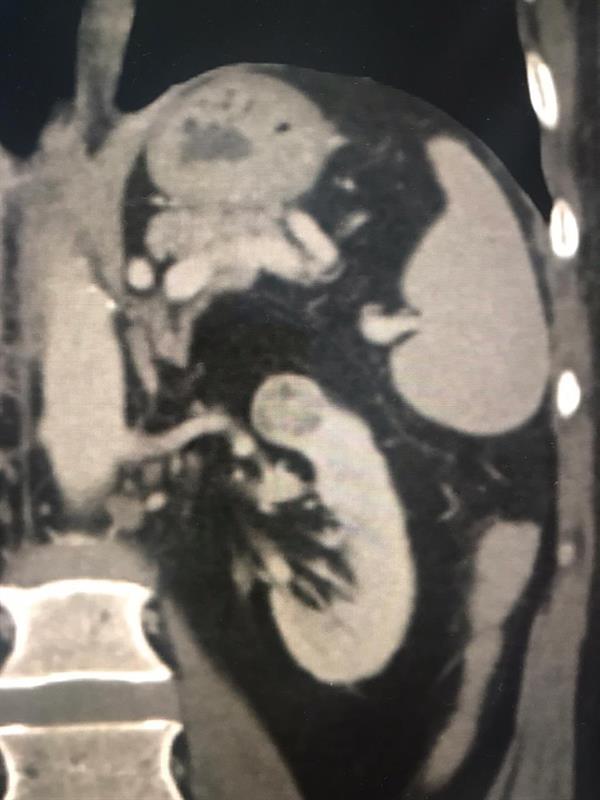

نجح فريق طبي بمدينة الملك عبدالله الطبية، من استئصال ورم سرطاني من الكلية اليسرى لمريض بالعقد السادس من العمر مع الحفاظ عليها وعلى وظيفتها بتقنية التبريد.

وأبانت مدينة الملك عبدالله الطبية، أن العملية تعد الأولى من نوعها على مستوى المنطقة الغربية، كما جرى تطبيق كافة الإجراءات الاحترازية الوقائية.